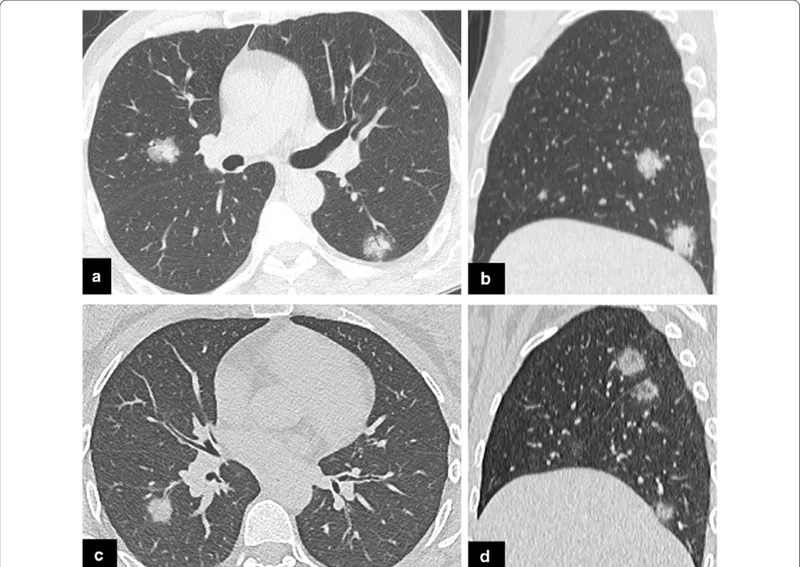

A chest X-ray showing community acquired pneumonia